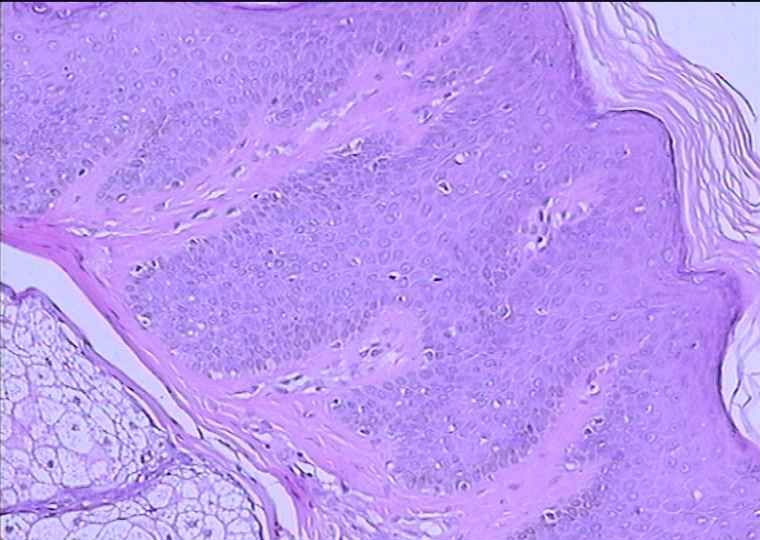

男 48岁 ,头部肿块48年(出生有),1CMX1CM,

皮脂腺痣

还是比较像皮脂腺痣。

出生就有故本例诊断皮脂腺痣

皮脂腺痣,不成熟的皮脂腺

典型皮脂腺痣!

表皮呈疣状增生,真皮内见到大量近乎成熟的皮脂腺

皮脂腺痣,表皮有增生